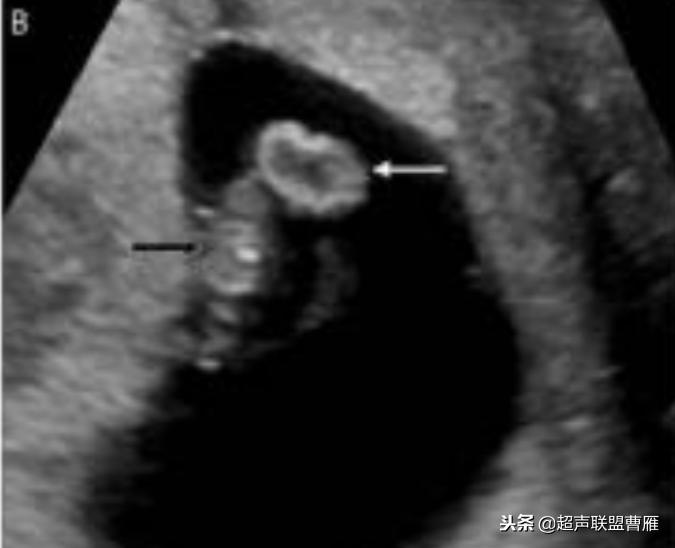

一个孕囊有两个卵黄囊,单卵双胎。

孕7周左右(胚芽11mm 卵黄囊)

宫内早孕 (7周左右)